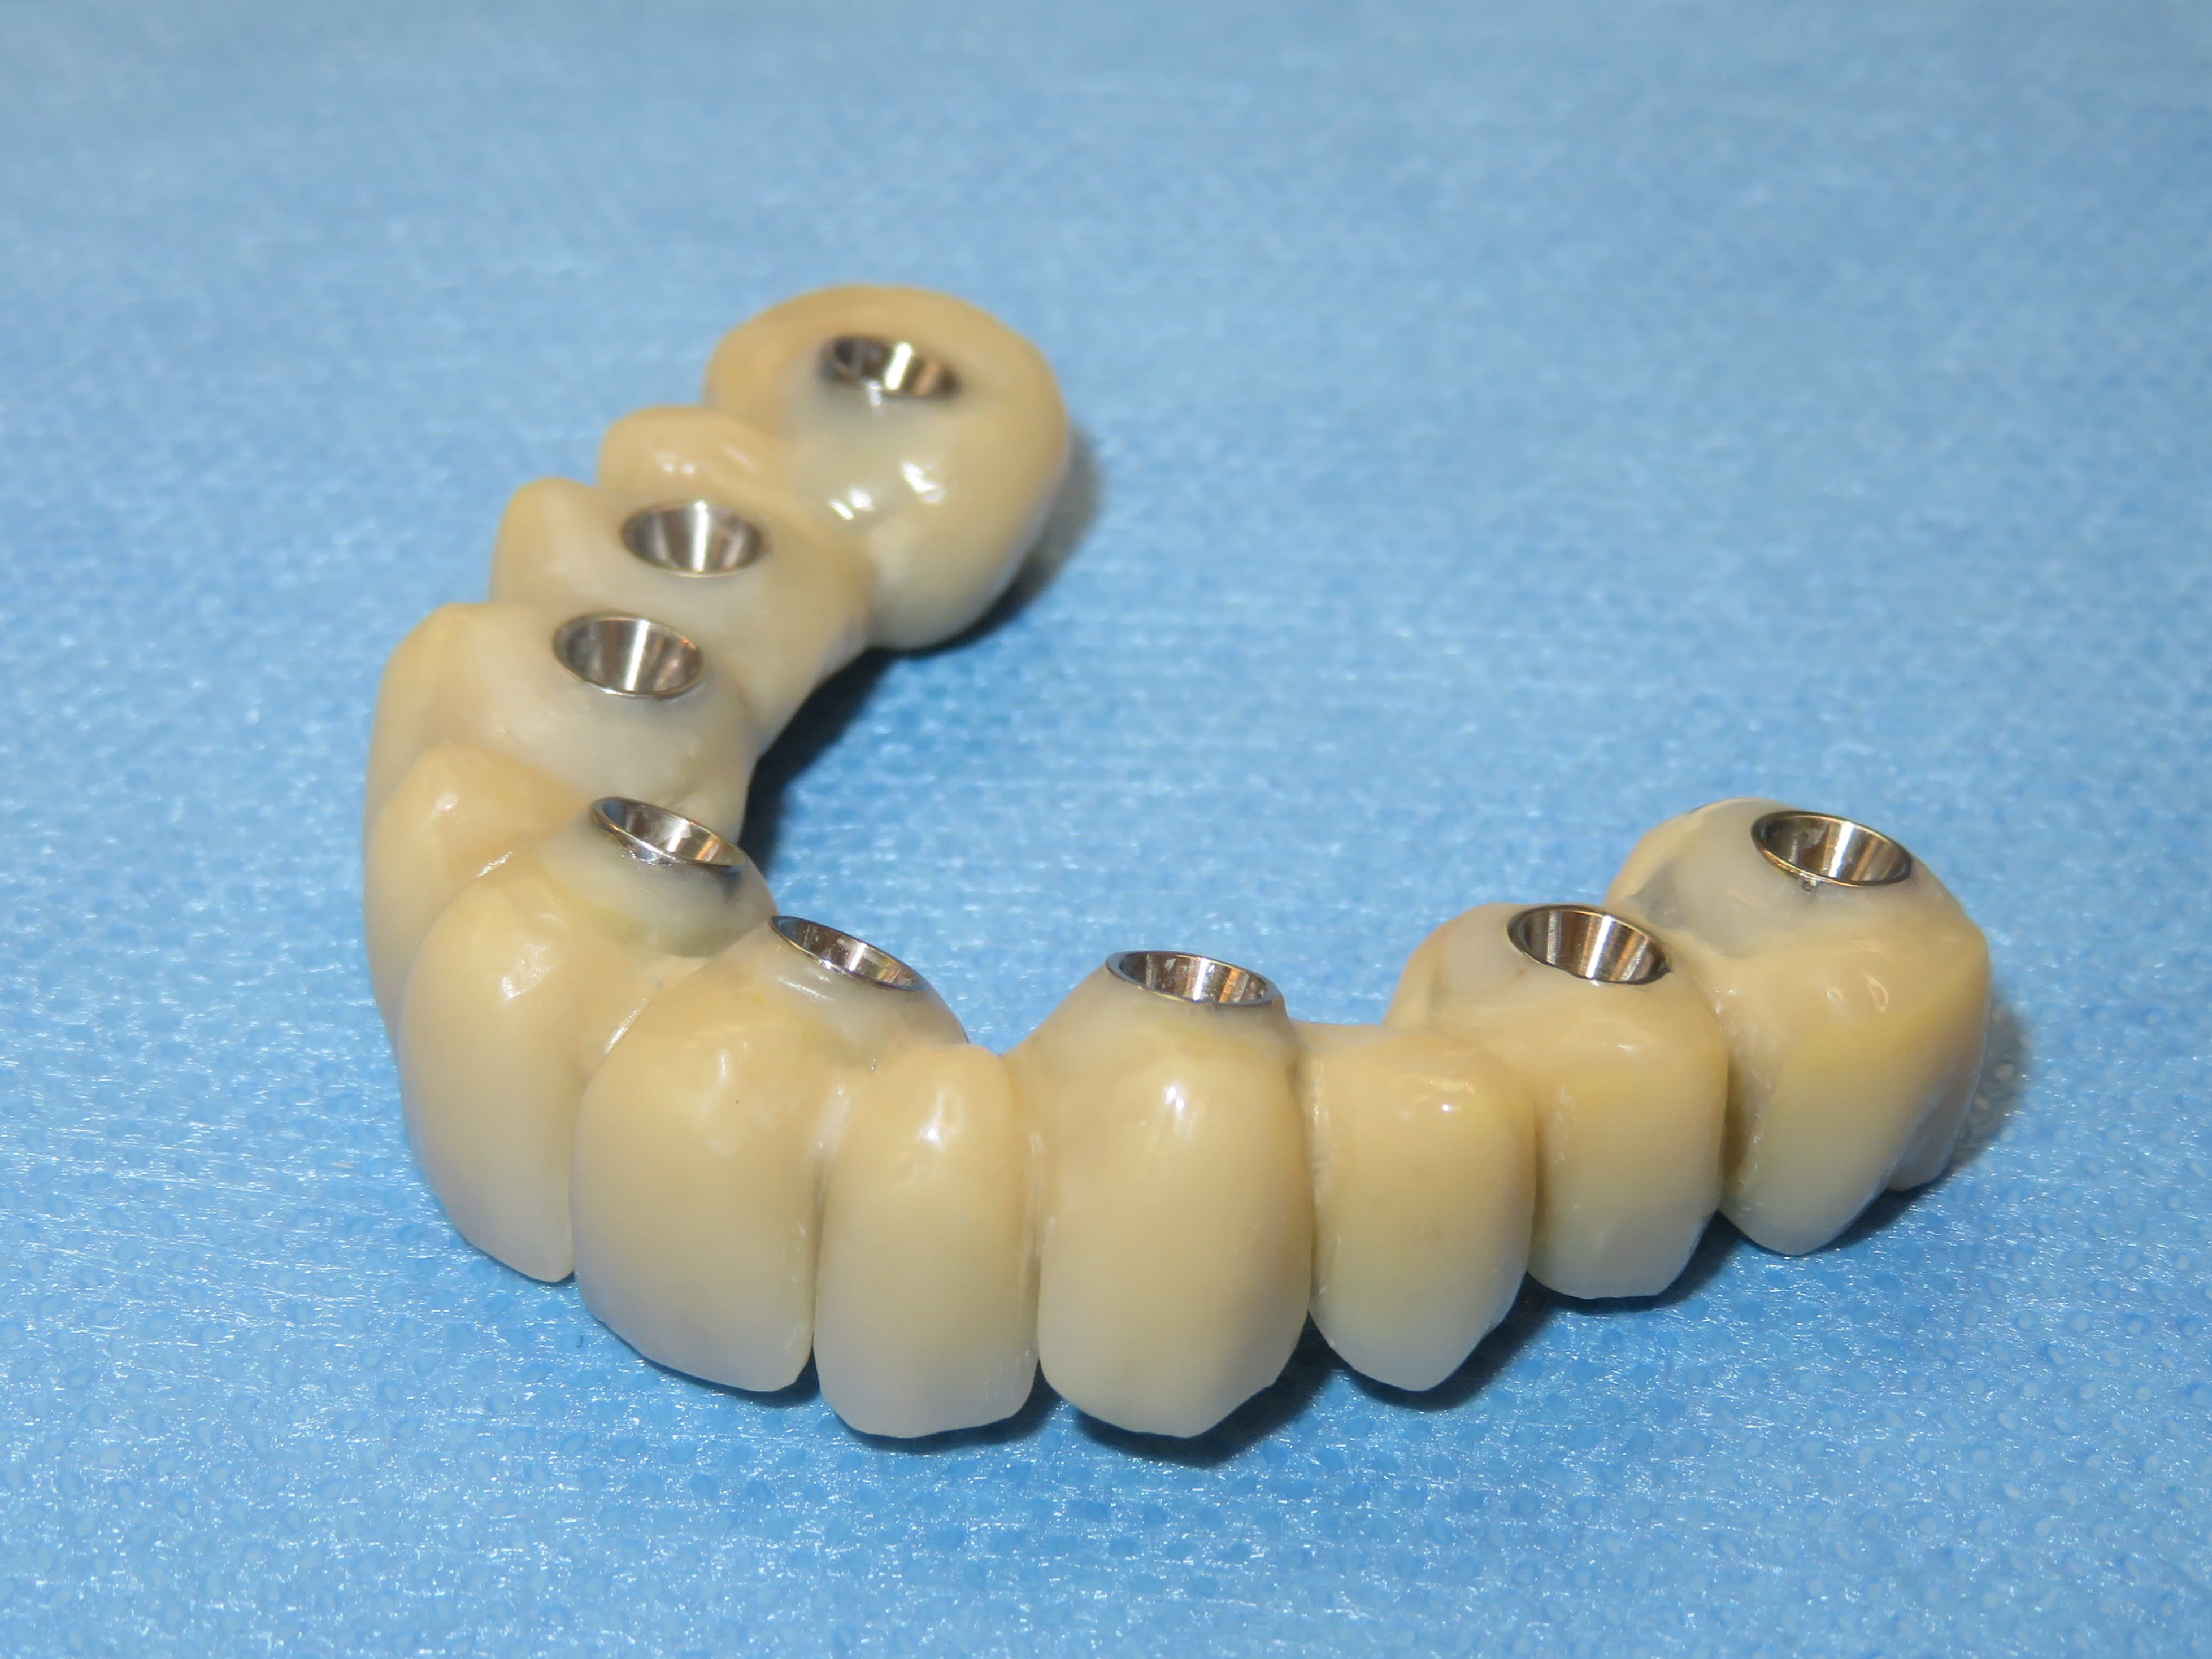

Autres cas de Dimitri : Quad zygo guidé, bridge full zircone tibase collé à l’avance.

Avec la zircone , le moindre défaut de passivité et le bridge est en deux …

Cela fait plus de deux ans qu’il utilise ce protocole.

Je crois que la, il n’y a plus de doute . Full zircone avec rosenscrew, pas de tibase .